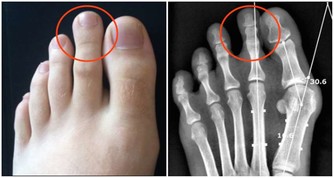

第三信號:腳疼

糖病足早期信號

濟南同濟吳峰醫生介紹說:當一些糖尿病患者出現行走一定距離後就腿痛、腳痛,就要留意了。許多人會把這些症狀當成是“老寒腿”,或者以為是腰椎疾病所致,其實出現這些症狀對於常人來說可能是一般的疾病,而對於糖尿病人來說,卻可能是糖尿病足的信號。

下肢動脈硬化

在我們身邊,經常會發現老年人走了一段路,就感覺自己腳有點兒疼,但不論是老年人自己還是周圍的親屬,首先想到的就是“會不會是腰間盤突出啊”?但實際上,在進入古稀之年後,越來越多的老人會患上下肢動脈硬化閉塞症或急性動脈栓塞。

濟南同濟吳峰醫生介紹說:下肢動脈硬化閉塞症,就是腿上的動脈血管由於動脈血管堵住了,導致腿腳供血不足,從而出現一系列症狀。一般就是不走路的時候還好,不覺得疼;一旦走路較多,就會出現腳疼、小腿酸痛。